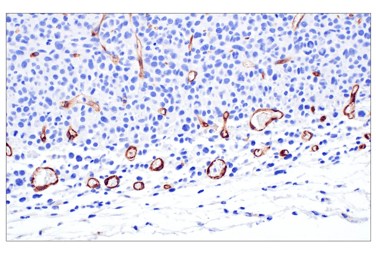

Successful metastasis to a new organ also requires tumor cells to exit the vasculature at specific “hot spots” of extravasation, where local endothelial activation and junction remodeling create sites for tumor escape into the surrounding tissue. These hot spots can be initiated both by local inflammatory cytokines and by tumor‑derived factors and extracellular vesicles that are delivered to distant organs, where they activate endothelial cells, increase vascular permeability, and help pre‑establish a permissive premetastatic niche. At these sites, tumor and monocyte-derived cytokines and chemokines promote endothelial activation and retraction, partly via E‑selectin upregulation, enabling transient adhesion of circulating tumor cells to the vessel wall.

Following this, stable adhesion is established through interactions between tumor cell integrins and adhesion molecules such as ICAM-1 (CD54) and ALCAM on endothelial cells, together with endothelial receptors including ICAM-1, VCAM-1, and lamin-rich basement membrane components that anchor adherent tumor cells to the vessel wall. Next, tumor-derived VEGF-A activates VEGFR signaling in endothelial cells. Downstream, FAK/Src signaling promotes VE‑cadherin phosphorylation and causes dissociation between VE‑cadherin and β‑catenin complexes at adherens junctions, leading to junction destabilization and opening paracellular routes for tumor extravasation.

![]() |

| IHC analysis of paraffin-embedded human urothelial carcinoma using CD54/ICAM-1 (E3Q9N) Rabbit Monoclonal Antibody #67836 performed on the Leica BOND RX. | IHC analysis of paraffin-embedded CT26.WT syngeneic tumor using VE-Cadherin (F4K3Y) Rabbit Monoclonal Antibody #60787. |

Together with local stromal and immune cells, these extravasation hot spots act as vascular exit points that disseminated tumor cells exploit to leave the circulation and begin colonizing distant tissues.